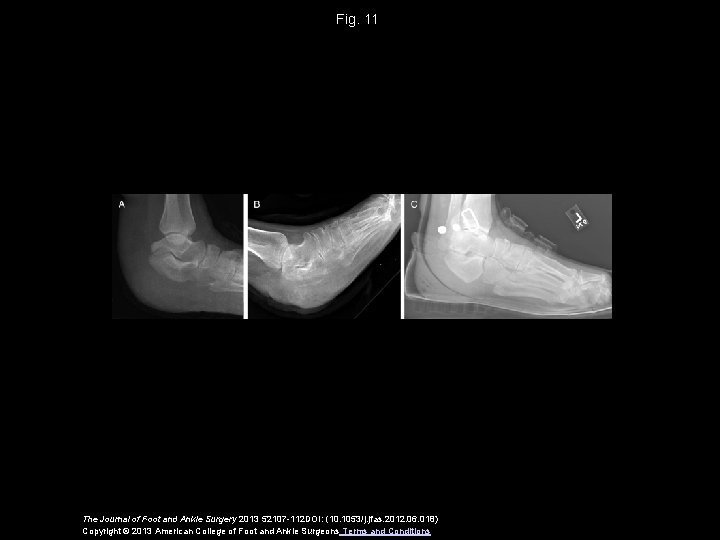

Fig. 11 The Journal of Foot and Ankle Surgery 2013 52107 -112 DOI: (10. 1053/j. jfas. 2012. 06. 018) Copyright © 2013 American College of Foot and Ankle Surgeons Terms and Conditions